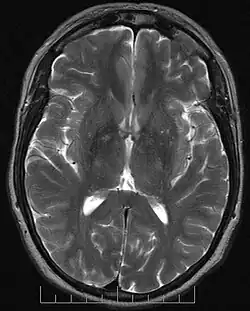

IRM standard : aucune voie neuronale ne peut être perçue dans cette coupe axiale haute résolution en séquence T2